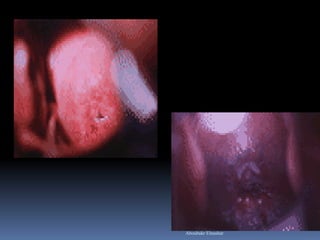

 VILI: test-positive

 Well-defined, bright yellow

iodine non-uptake areas

touching the SCJ